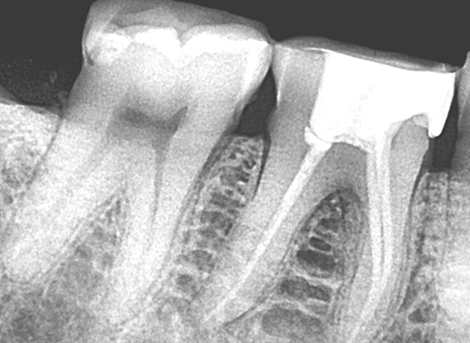

Sealing the Canal

Restoration